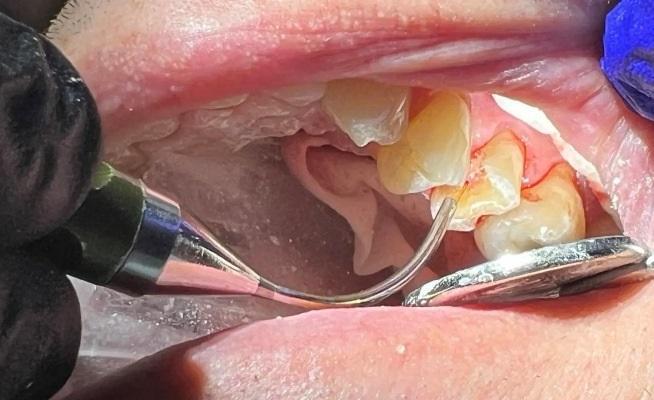

Сразу после контакта с пульпой, использовался Nd:YAG-лазер в режиме абляции (4,6 Вт, 100 мкс, 230 МДж, 20 Гц) на область воздействия при 50-75 Дж, чтобы остановить кровотечение и закрыть область воздействия, не проникая в пульпарную камеру более чем на 3 мм (фото 6). Затем на тех же настройках лазер использовался с мощностью 162 Дж для стерилизации окружающих структур зуба и биостимуляции для активации стволовых клеток, повышения репаративной активности дентина и снижения уровня простагландинов в послеоперационном периоде. Когда обработанный участок зуба был стерильным, перед нанесением покрытия на дентин и пульпу были приняты меры по предотвращению загрязнения. Сразу использовали небольшое количество стеклоиономерного цемента GC FujiCEM (GC America, фото 7). Затем была выполнена реконструкция культи зуба с использованием смолы RelyX Unicem (3M ESPE) на окружающих здоровых участках зуба для обеспечения хорошего сцепления между материалом культи и дентином. Подготовка коронки была завершена (фото 8). С помощью сканера TRIOS (3Shape) был снят цифровой слепок, изготовлена временная коронка и зацементирована с помощью цинкоксидэвгенольного цемента IRM (Dentsply Sirona). Окончательная коронка была установлена и закреплена через две недели, пациент сообщил об отсутствии чувствительности, так как лечение проводилось при воздействии пульпы.

Фото 6: Обработка пульпы с помощью Nd:YAG-лазера для устранения любых бактерий, которые могли привести к инфицированию пульпы и потребовали бы эндодонтического лечения.